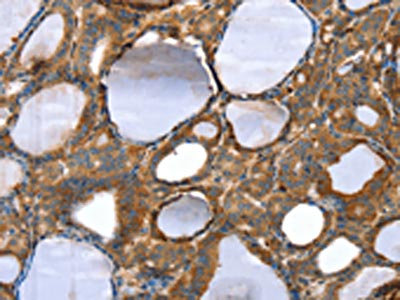

The image on the left is immunohistochemistry of paraffin-embedded Human esophagus cancer tissue using CSB-PA180088(TAGLN Antibody) at dilution 1/30, on the right is treated with fusion protein. (Original magnification: ×200)

The image on the left is immunohistochemistry of paraffin-embedded Human thyroid cancer tissue using CSB-PA180088(TAGLN Antibody) at dilution 1/30, on the right is treated with fusion protein. (Original magnification: ×200)